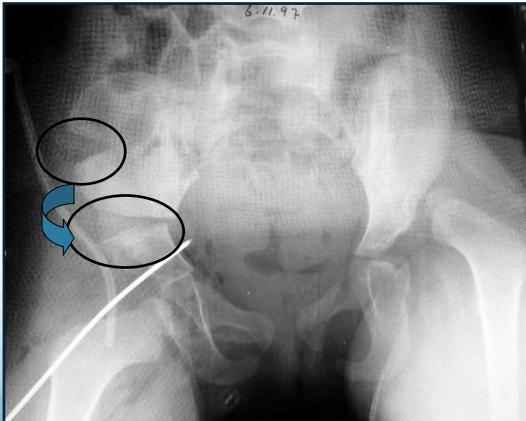

1. Horizontal Line Through Tri-radiate Cartilage

- Normal: Femoral head ossific center below the horizontal line

- Dislocated: Femoral head ossific center above the horizontal line

2. Perpendicular Line from Acetabular Edge

- Normal: Femoral head ossific center medial to perpendicular line

- Dislocated: Femoral head ossific center lateral to perpendicular line

4. Shenton’s Line

- Important assessment tool for hip joint integrity